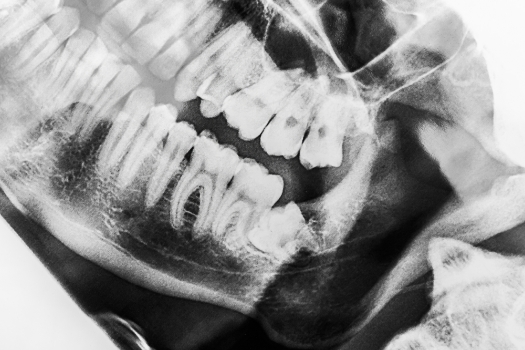

最近はデンタルケア用品のCMなどで「歯の再石灰化」という言葉がよく使われています。「再石灰化」とは、酸によって歯から溶け出したカルシウムなどが歯に再び吸収される現象。歯質が元の状態に回復するという意味では「虫歯が治る」と思われがちですが、再石灰化で治癒が期待できるのはごく初期の虫歯のみ。そのうえ、ごく初期の虫歯かどうかは専門家にしかわかりません。“治療が必要”にならないよう、お口の異変を感じたらなるべく早く相談にお越しください。